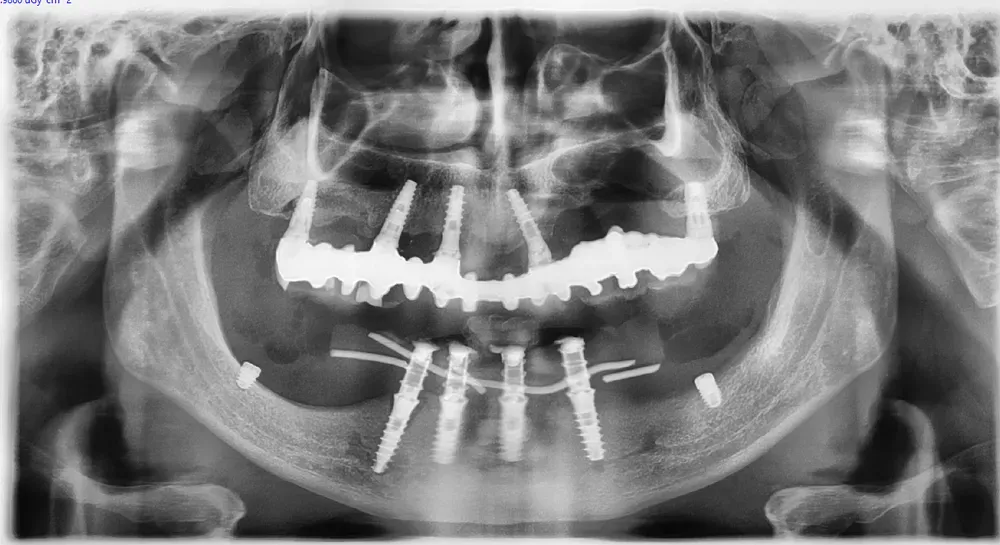

Le immagini radiografiche che seguono testimoniano alcune delle tante soluzioni tecniche che ho utilizzato per le arcate a carico immediato nel corso della mia carriera. Ogni caso presenta sfide diverse e richiede un approccio personalizzato.

Anche nei pazienti anziani con protesi mobili (dentiere) che presentano condizioni critiche dal punto di vista osseo, gli interventi di implantologia a carico immediato possono essere portati a termine con successo.

Tutto dipende dalle condizioni di salute generale e dall’anatomia residua. Non esiste un limite di età assoluto, ma solo una valutazione attenta del rapporto rischio-beneficio per ogni singolo paziente.